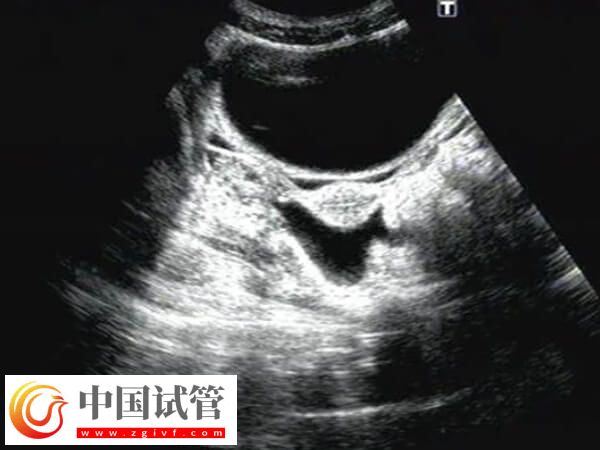

試管囊胚移植40天宮腔有積液的干凈時(shí)間不可一概而論,還需要根據(jù)實(shí)際情況進(jìn)行判斷,畢竟每個(gè)患者身體情況不同多樣積液消失時(shí)間也會(huì)有差異,建議出現(xiàn)宮腔積液的患者,應(yīng)該定期進(jìn)行超聲檢查,監(jiān)測(cè)積液的變化,然后根據(jù)醫(yī)生的建議進(jìn)行適當(dāng)?shù)谋Lゴ胧?/h5>囊胚移植后子宮積液怎樣能排出